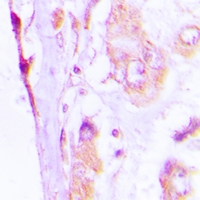

IHC (Immunohiostchemistry)

(Immunohistochemical analysis of CAP18 staining in human lung cancer formalin fixed paraffin embedded tissue section. The section was pre-treated using heat mediated antigen retrieval with sodium citrate buffer (pH 6.0). The section was then incubated with the antibody at room temperature and detected using an HRP conjugated compact polymer system. DAB was used as the chromogen. The section was then counterstained with haematoxylin and mounted with DPX.)